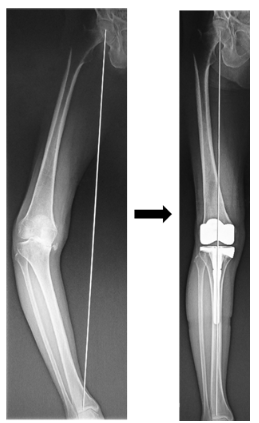

関節リウマチや変形性膝関節症によって軟骨がすり減り、鎮痛薬や関節注射などの保存療法を受けても膝の痛みが緩和されない患者様には人工関節置換術を数多く実施しています。また人工関節置換術だけではなく、ご自身の膝関節温存を希望される患者様には膝周囲骨切り術も積極的に行っています。ただしどちらの手術も長所と短所がありますので、主治医とよく相談して治療法を選択することをお勧めします。

人工膝関節置換術前と術後のレントゲン写真

高位脛骨骨切り術前と術後のレントゲン写真

東海大学では変形性膝関節症に対して高位脛骨骨切り術を併用した自己細胞シート移植による軟骨再生治療が先進医療Bとして承認されており、これまで12名の患者様に移植手術を行っております。また手術に至る前段階として多血小板血漿(PRP)の関節内注射による変形性膝関節症治療にも積極的に取り組んでいます。